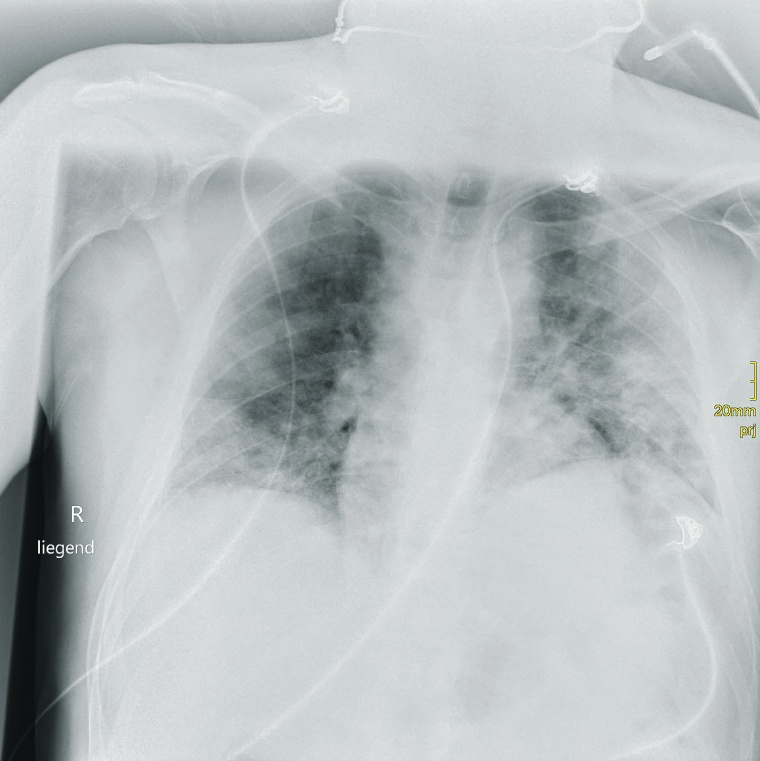

Prof. Dr. Stephan Kloska: Durch unsere sehr aktive Notaufnahme haben wir einen großen Anteil an Patienten mit eingeschränkter Mobilität und nachts ist manchmal nur eine MTRA im Einsatz. Darum brauchen wir ein System, bei dem die Patienten einfach und auch von einer Person alleine umgelagert werden können. Da kommt uns die Funktionalität des Adora-Systems, bei dem keine Umlagerung in der 2. Ebene erforderlich ist, sehr entgegen. In der ersten Pandemiewelle wurden rund 50 % der COVID-19-Fälle der Region im Klinikum Fürth behandelt, in Hochzeiten waren es bis zu 90 stationäre Patienten. Gerade in dieser Phase, wo der Andrang mit Patienten auf COVID-Verdacht ausgesprochen groß war und ist und wir schnell nach COVID-Patienten und Verdachtsfällen vorsortieren mussten, konnten wir mit dem Adora-System in der Notaufnahme sehr schnell agieren.

Kloska: Grundsätzlich kann man sagen, dass es die Überlegungen, auf ein volldigitales System umzusteigen, schon länger gab. Aber Corona hat die Anschaffung noch einmal maßgeblich beschleunigt.

Kloska: Die mobilen Geräte haben Handling und Workflow deutlich verbessert. Das alte System stieß an seine Grenzen. Gerade in den COVID-Bereichen sind wir viel mobil unterwegs, weil sich die Mitarbeiter so nur einmal umziehen müssen. Beim alten System haben wir eine Kassette pro Patient benötigt, die ausgelesen werden musste. Jetzt sparen wir uns den umständlichen Kassettenwechsel und über die wireless verfügbaren Worklists können die Daten außerdem direkt den einzelnen Patienten zugeordnet werden.

Bayer: Mit den Motor betriebenen Einheiten sind wir schnell im Haus unterwegs. Und das System passt mühelos in den Fahrstuhl, das ist ein wichtiges Argument. So können wir zügig die einzelnen Aufträge aus den Stationen erfassen und abarbeiten. Damit das mobile Röntgen nicht inflationär genutzt wird, machen die MTRAs mittlerweile jeweils eine „Röntgen-Runde“ für elektive COVID-Röntgenfälle am Vor- und eine am Nachmittag.